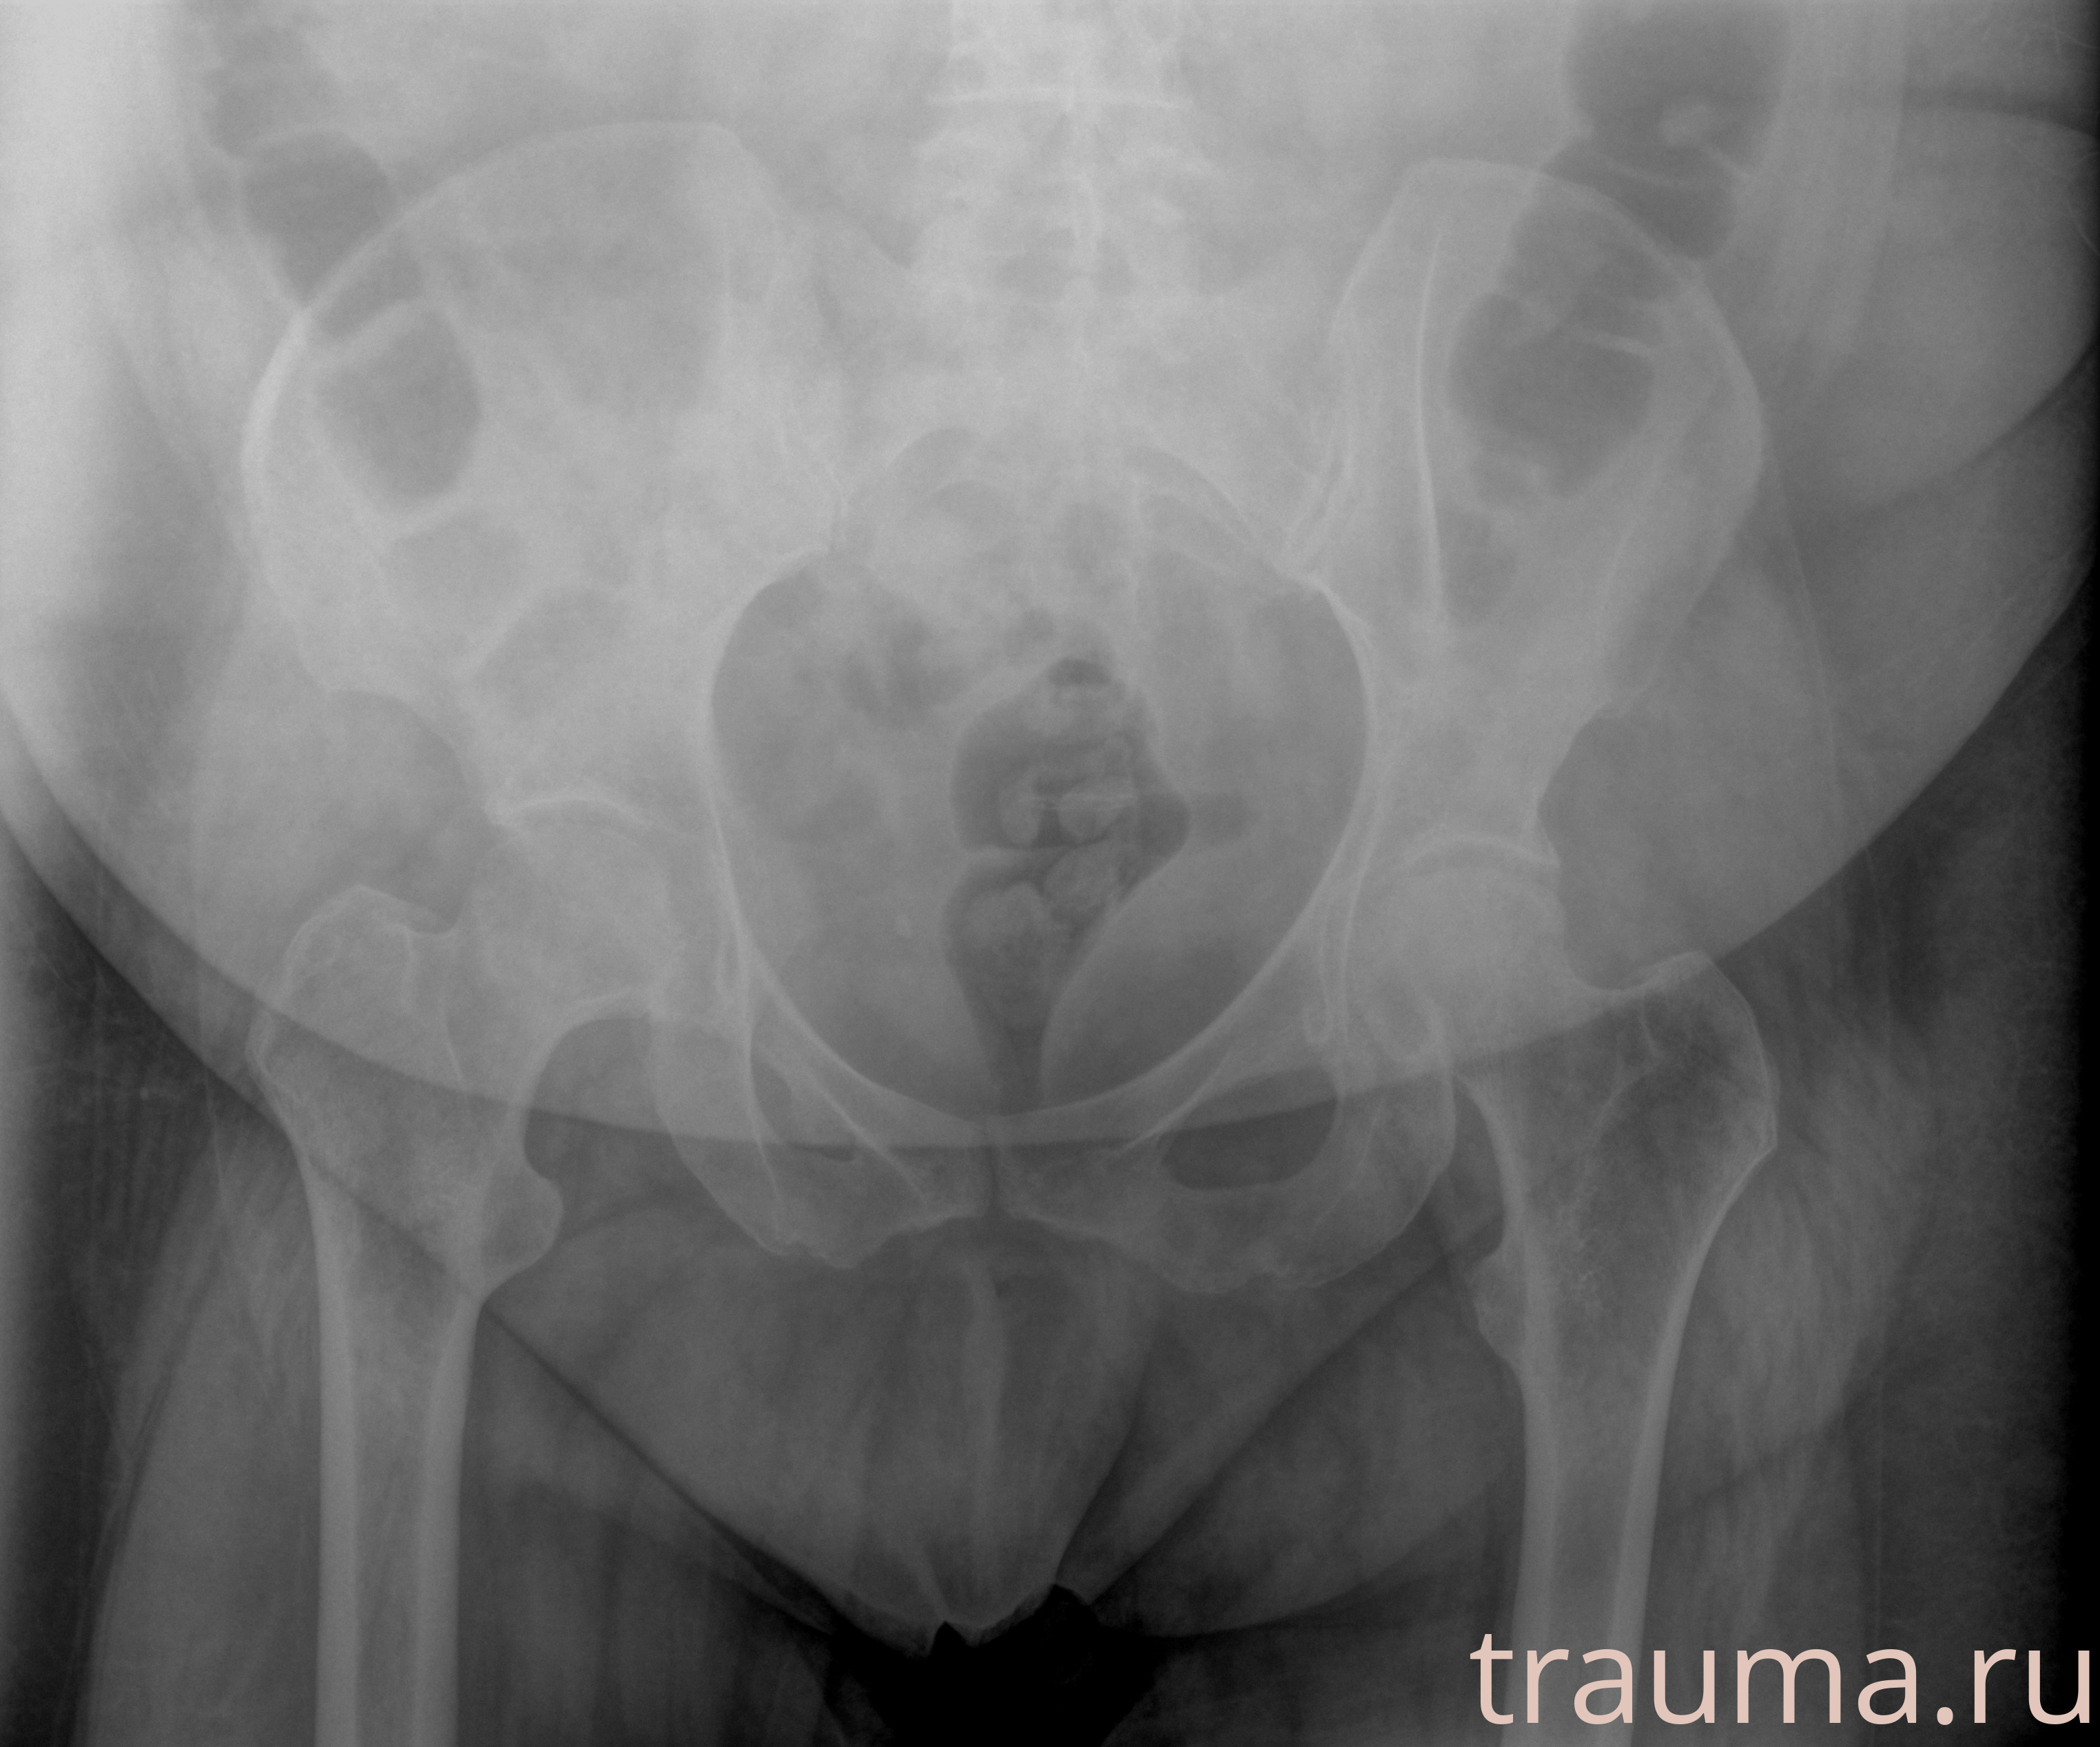

Рентген на дому: по вашему адресу приезжает врач-рентгенолог, травматолог-ортопед с мобильным рентгеновским аппаратом, проводит диагностику травмы или заболевания, делает необходимые рентгенограммы, дает рекомендации по дальнейшему лечению. Получить качественные снимки в домашних условиях возможно благодаря уникальной методике, разработанной МосРентген Центром для института  Склифосовского